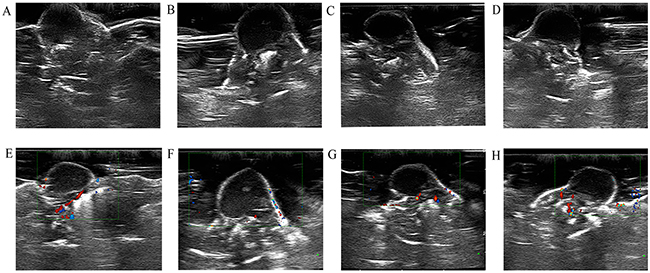

Before irradiation, the skin surface above the subcutaneous pancreatic cancer xenografts in nude mice was undamaged. After irradiation, no mice had skin burns in Group A or Group B, but seven mice in Group C had skin burns. Before irradiation, the skin over the xenografts was hyperechoic. The interior part of the xenografts exhibited low or very low echo. The internal echo of the tumors was homogeneous.(Figure 2A). Color Doppler flow imaging showed that the pancreatic cancer xenografts had no significant internal flow. The flow signals of the tumor-feeding vessels were detected in the periphery of xenografts, and arterial and venous spectra were detected (Figure 2E). CEUS images revealed that at approximately 4 to 6 seconds after bolus injection of the contrast agent, the interior portion of the xenografts showed perfusion with heterogeneous enhancement (Figure 3A). The degree of enhancement was higher than that of the surrounding muscles. At 12 to 15 seconds after injection, the contrast agent inside the tumors began to be expurgated, showing the typical malignant tumor enhancement mode of rapid entry and rapid exit.

Figure 2: B-mode US and color Doppler flow imaging obtained before HIFU irradiation (A and E). B-mode US image obtained at 24 hours, 48 hours, and 2 weeks after HIFU irradiation (B, C, and D). Color Doppler flow imaging obtained at 24 hours, 48 hours, and 2 weeks after HIFU irradiation (F, G, and H).

Within 24 hours of HIFU irradiation, the interior of the xenografts showed no significant changes on B-mode US examination, still exhibiting low or very low echo. Some xenografts had small patches of slightly high echo inside the tumors (Figure 2B). Color Doppler flow imaging revealed no significant detectable blood flow within the xenografts, but the periphery of the xenografts showed visible dot-like flow signals (Figure 2F). CEUS revealed contrast agent perfusion at the periphery of the tumors, as well as irregular un-perfused areas within the tumors (Figure 3B). The histological result suggested that cells within the ablation lesions showed apoptosis and necrosis 24 hours after HIFU irradiation. There were no clear boundaries between the injured areas and the surrounding normal tumor cells. Because of the expansion of microvascular congestion within the xenografts at the early stage after irradiation, multiple small vessel ruptures occurred within the ablation lesions (Figure 4A). As shown in the Figure 4D, 4E, and 4F, some cells within the ablation lesions showed apoptosis 24 hours after HIFU irradiation. Apoptotic nuclei showed clear brown staining, suggesting the formation of DNA fragments (Figure 4D). Clear chromatin margination was observed in the nuclei, and formation of apoptotic bodies in the cells was also observed. At 48 hours after HIFU irradiation, B-mode US examinations demonstrated low or very low echo within the tumors (Figure 2C), with no significant changes compared with the pre-treatment conditions. Color Doppler flow imaging did not reveal significant blood flow within the tumors, and the dot-like blood flow signals in the xenograft periphery were decreased. (Figure 2G). The CEUS results were like those of the 24-hours group, with irregular un-perfused areas within the tumors and contrast agent perfusion in the tumor periphery (Figure 3C). At 48 hours after HIFU irradiation, ablation lesions gradually showed clear boundaries. The distribution of small blood vessels within the ablation lesions was reduced, and cellular structures were damaged and became fuzzy. Tissues in the target areas showed large patches of necrosis and apoptosis (Figure 4B). At 48 hours after HIFU irradiation, the ablation lesions still contained many apoptotic and necrotic cells (Figure 4E).

At 2 weeks after HIFU irradiation, B-mode US demonstrated that the echo within the tumor was not significantly increased (Figure 2D). Color Doppler flow imaging showed that the blood flow signals in the periphery of xenografts were increased (Figure 2H). CEUS revealed un-perfused areas within the tumors that enlarged with time after HIFU irradiation. The peripheral contrast agent perfusion area was increased compared with the 24-hours and 48-hours groups (Figure 3D). At 2 weeks after HIFU irradiation, the tissues in the ablation zone showed homogeneous cellular structures. The tissues exhibited significant organization and fibrosis. Tissue dissolution and absorption were found between necrotic tissues, leading to the formation of small cavities (Figure 4C). At 2 weeks after HIFU irradiation, the number of apoptotic cells decreased in the ablation lesions. Only a small number of necrotic cells remained, with nuclear condensation and dark brown-stained nuclei (Figure 4F).